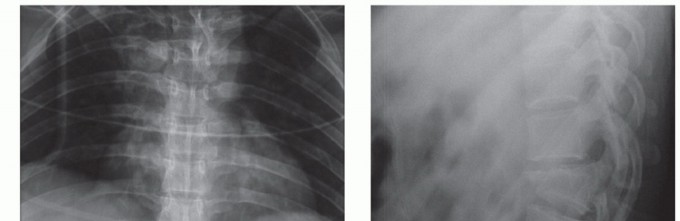

SURGICAL MANAGEMENT Operative intervention in the posterior subaxial cervical spine is frequently carried out…